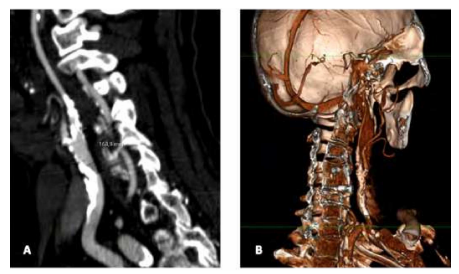

A computed tomography angiogram of the head and neck was performed revelling a significant morphologic stenosis of the left common carotid artery, left internal carotid artery with sub occlusive disease and right internal carotid artery stenosis estimated at 70-75%, both calculated with the North American Symptomatic Carotid Endarterectomy Trial (NASCET) method (Figure 1, A and B). The vertebral arteries study did not reveal significant morphologic disease and circle of Willis was patent.

Figure 1 Pre-operative computed tomography angiogram. A - stenosis of the left common and internal carotid artery (longitudinal section); B - Volume rendering reconstruction of left carotid bifurcation (internal projection).